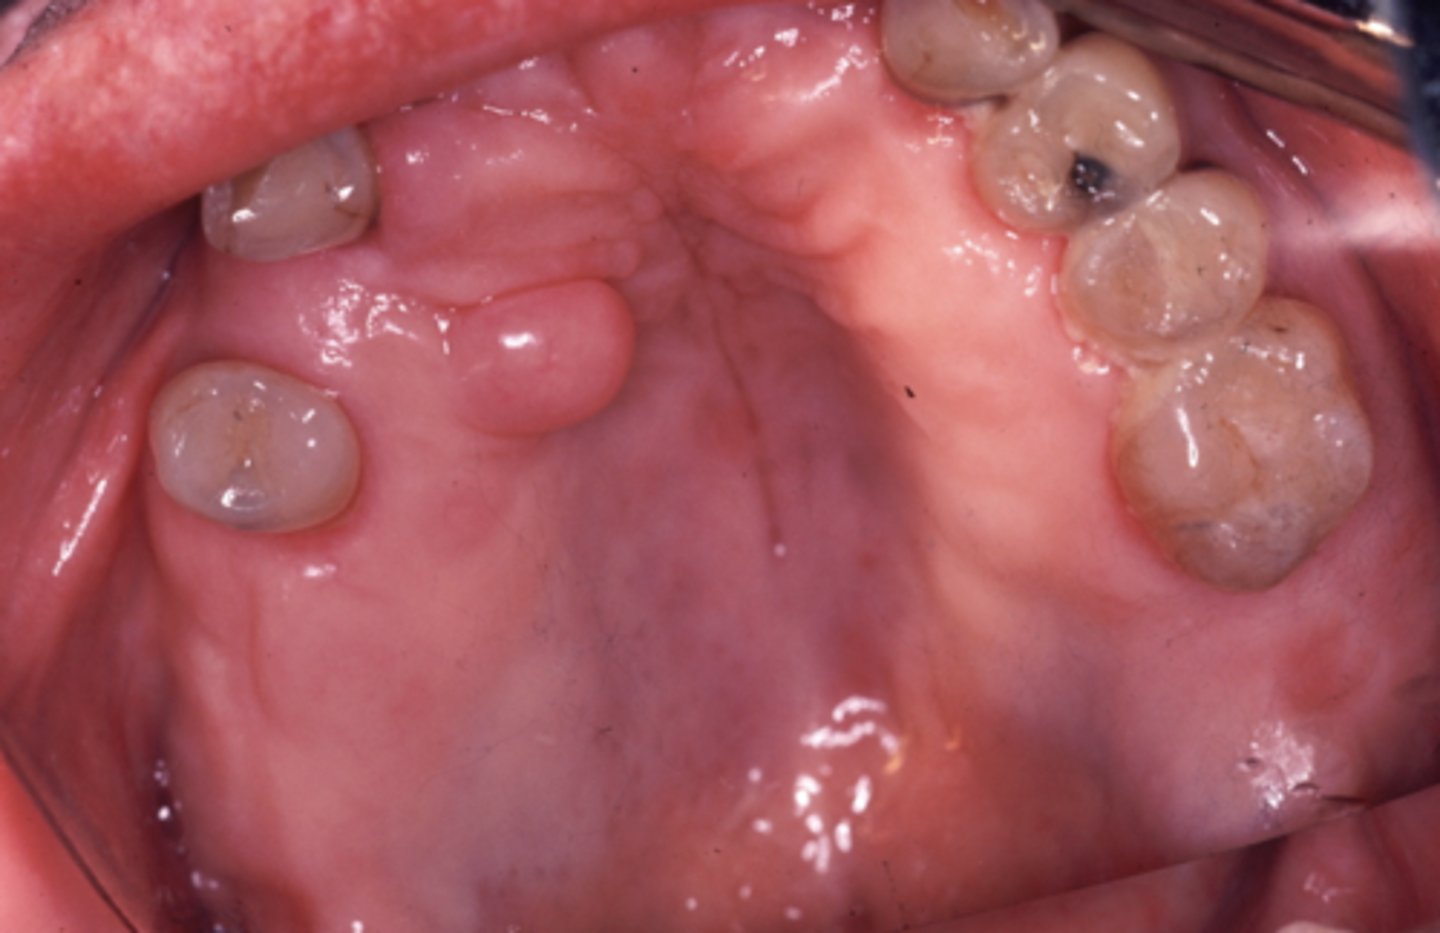

what is congenital epulis of the newborn?

proliferation of granular cells that appears as a soft, round, exophytic mass attached to the alveolar mucosa

congenital epulis is more common in (males/females)

females

congenital epulis is more common on the (maxilla/mandible)

maxilla

T/F: pseudoepitheliomatous hyperplasia (PEH) is found in congenital epulis

false